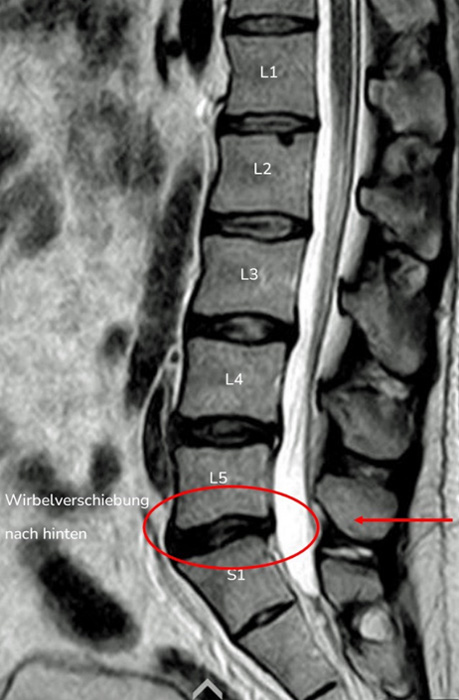

2. Beispiel – Wirbelverschiebung nach hinten

Auch bei dieser Aufnahme kann man Ähnlichkeiten zwischen der MRT-Aufnahme und der Konturdarstellung der Medi Mouse erkennen.

Bei dieser Wirbelsäulenform ist die normale Lordose der Lendenwirbelsäule nicht vorhanden, das Gegenteil ist der Fall, die Kyphose ist bis zum Kreuzbein verlängert.

Dies als Folge einer Rückverlagerung des Oberkörpers, was dazu führt, dass das eine Knicktendenz nach hinten entsteht und die Wirbelverschiebung nach hinten begünstigt.

Wirbelverschiebung Medi-Mouse

Wirbelverschiebung MRI